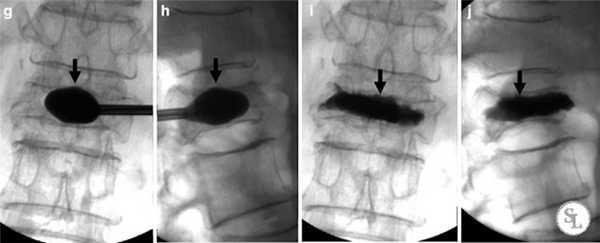

Операция проводится под общим наркозом, хотя в некоторых случаях, когда такой вид анестезии может нанести пациенту вред, ее выполнение допускается под местным анестезиологическим обеспечением. Кифопластика проводится следующим образом:

- Пациент располагается на операционном столе. С помощью рентген-аппарата нейрохирург точно определяет точку доступа в проекции ножки дужки пораженного позвонка.

- Выполняется разрез, длина которого не превышает 1 см.

- Под рентген-контролем вводится специальная полая игла так, чтобы она прошла точно между телом пораженного позвонка и ножкой дуги.

- Через иглу вводится направляющая спица до тех пор, пока она не упрется в переднюю замыкательную пластину. После этого иглу-проводник можно удалить.

- С помощью спицы устанавливается диссектор с тупым концом и рабочая канюля. Именно через эту канюлю нейрохирург будет проводить все необходимые манипуляции. Поэтому ее установке уделяют особое внимание. Ее краевой элемент должен располагаться кпереди от задней хрящевой пластинки, закрывающей тело позвонка. Как только спинальный хирург добьется этого, диссектор осторожно удаляют.

- Специальным стилетом или сверлом формируется канал в позвонке, через который в дальнейшем в него будет погружаться раздуваемый баллон из эластичного материала.

- Под рентген-контролем в созданную полость вводят сдутый баллон. Поскольку он создан из рентгенконтрастных материалов, его четко видно внутри позвонка. Это позволяет мгновенно оценить правильность установки баллона, глубину и его положение.

- К канюле присоединяется шприц с физраствором с добавлением контрастного вещества, имеющий измерительную систему контроля не только над объемом жидкости, но и давлением ее подачи. Баллон постепенно наполняют, постоянно контролируя параметры тела позвонка.

- После достижения анатомически правильной геометрии и восстановления размеров вертикальной оси деформированного позвонка баллон опорожняют и удаляют из организма.